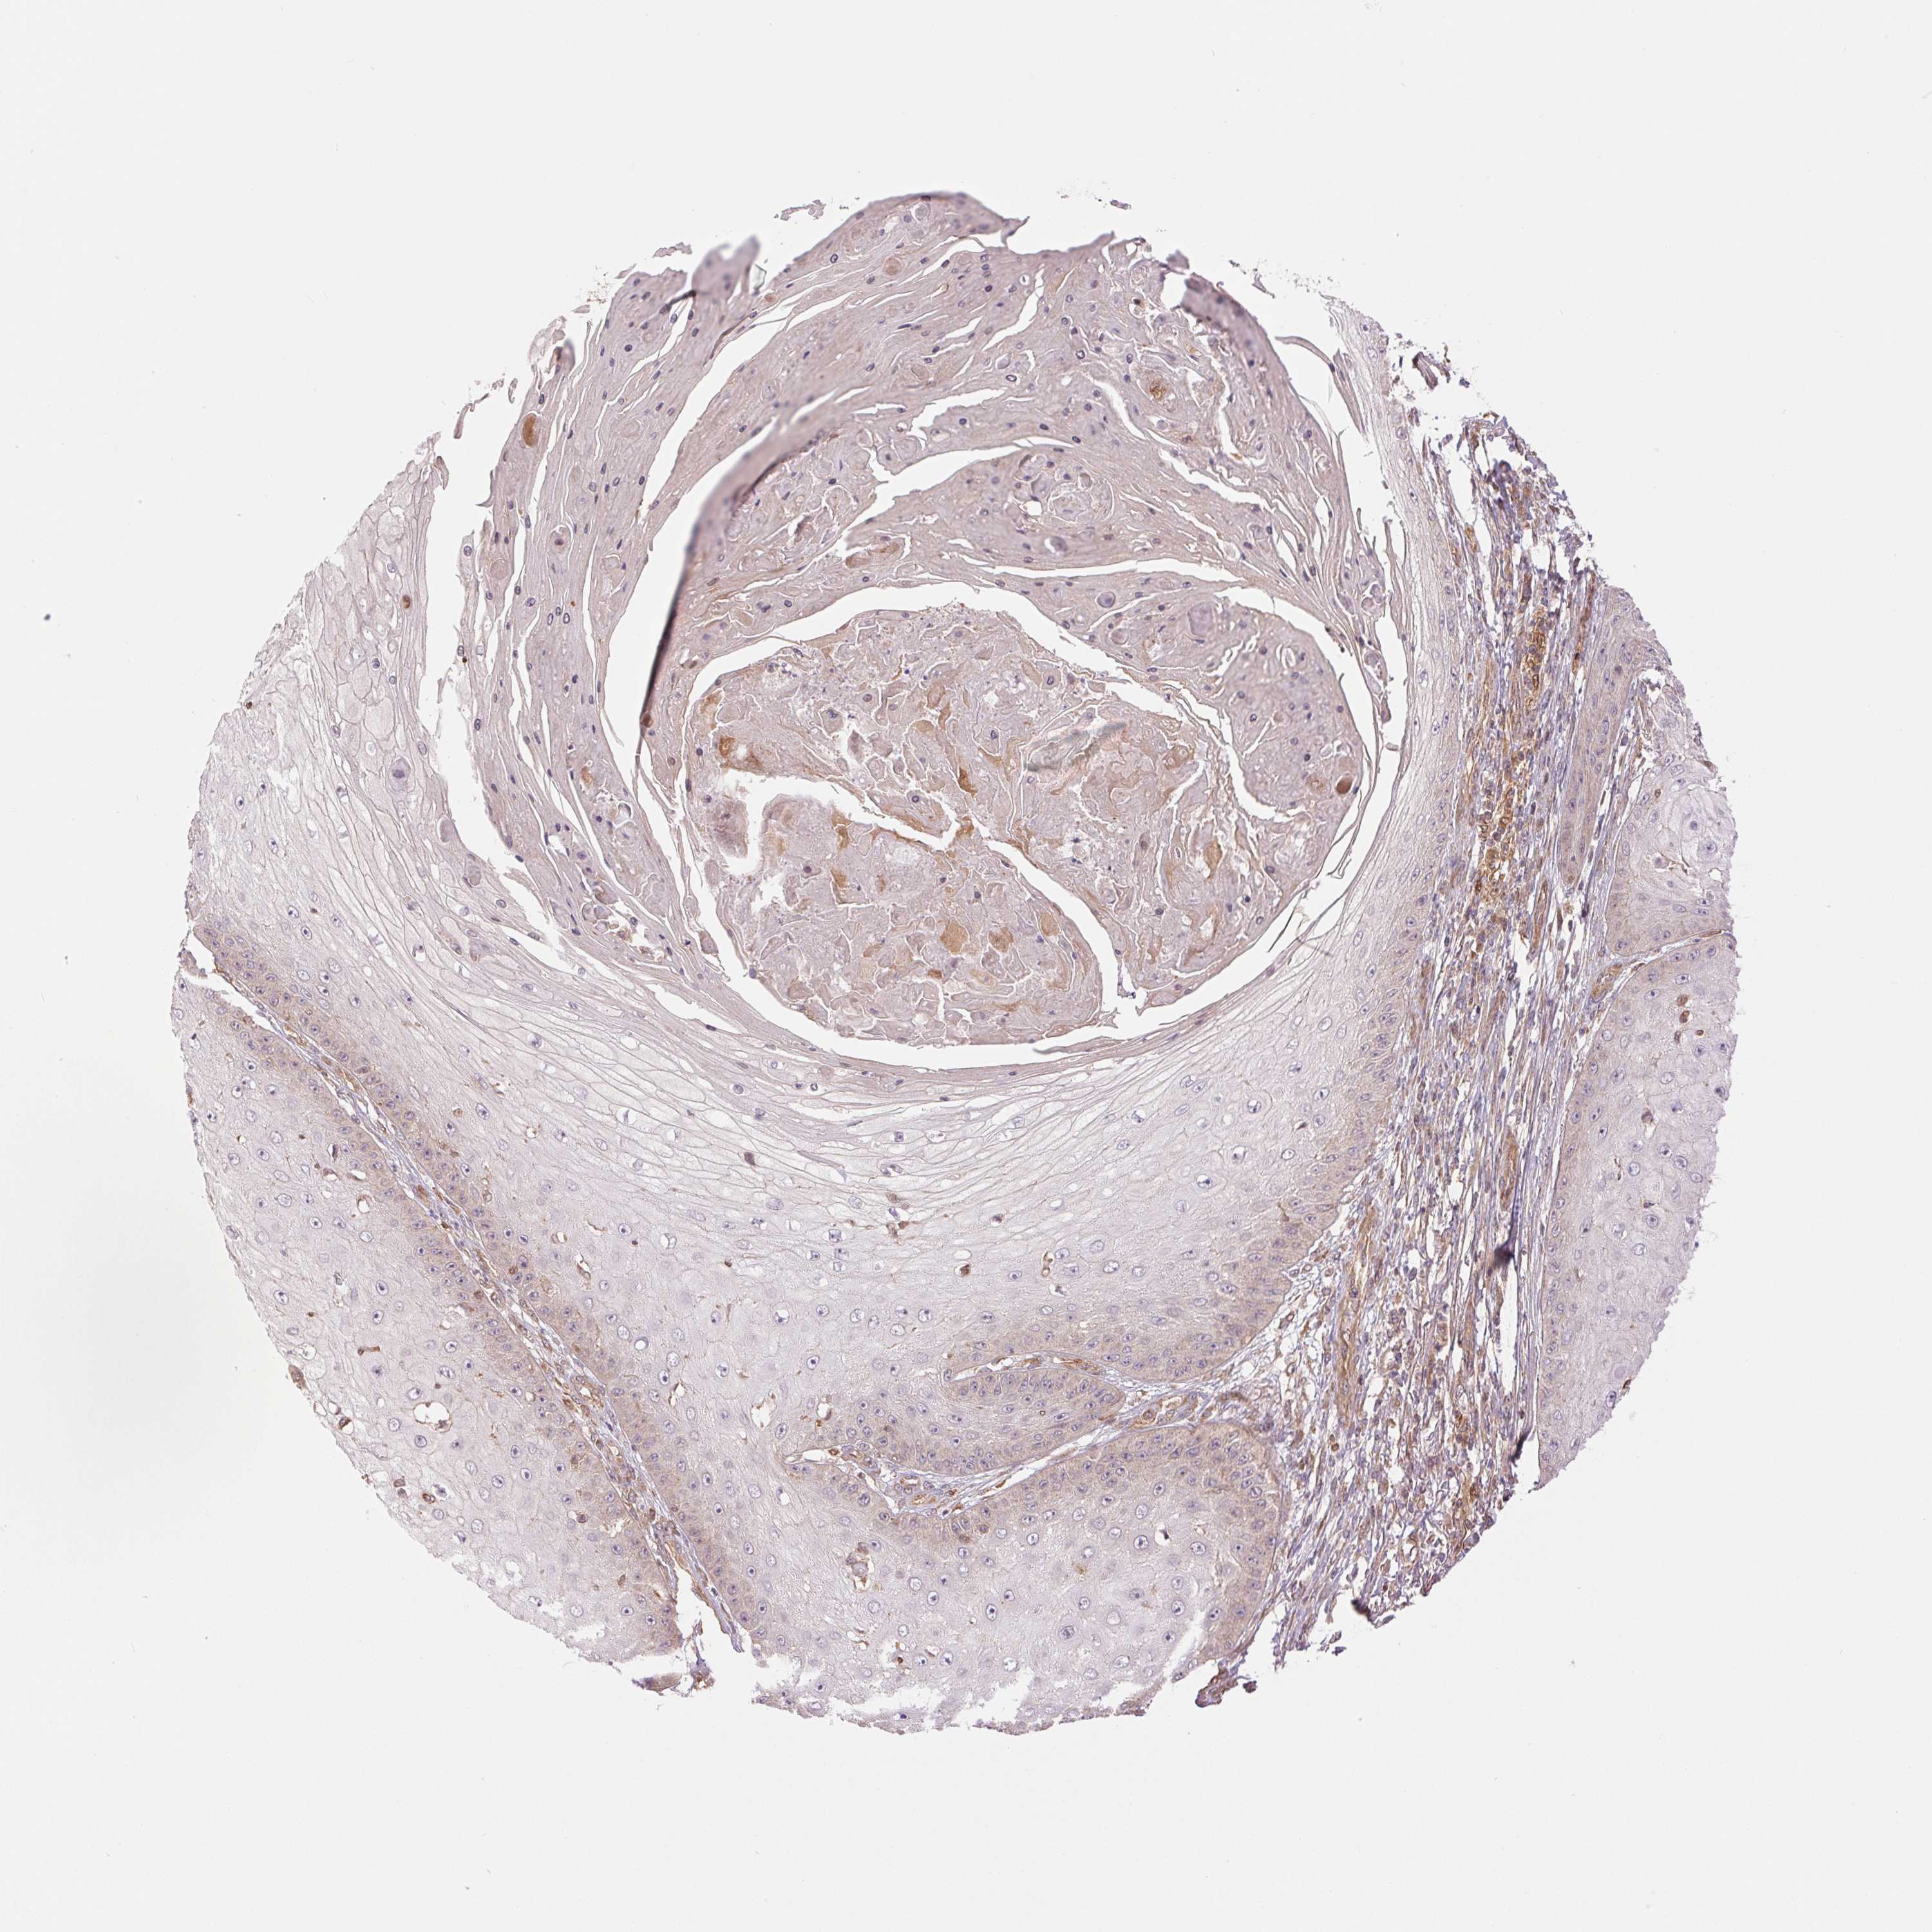

Basal cell and squamous cell cancer

SKIN CANCER - Protein expressioni

A mouse-over function shows sample information and annotation data. Click on an image to view it in a full screen mode. Samples can be filtered based on level of antibody staining by selecting one or several of the following categories: high, medium, low and not detected. The assay and annotation is described here.

Antibody stainingi

Antibody staining in the annotated cell types in the current human tissue is reported as not detected, low, medium, or high, based on conventional immunohistochemistry profiling in selected tissues. This score is based on the combination of the staining intensity and fraction of stained cells.

Each image is clickable and will lead to virtual microscopy that enables deeper exploration of all samples and also displays staining intensity scores, fraction scores and subcellular localization as well as patient and tissue information for each sample.

Antibody HPA064978

Antibody CAB033965

Staining

High

Medium

Low

Not detected

Intensity

Strong

Moderate

Weak

Negative

Quantity

>75%

75%-25%

<25%

None

Location

Nuclear

Cytoplasmic/membranous

Cytoplasmic/membranous,nuclear

Basal cell carcinoma

Squamous cell carcinoma, NOS